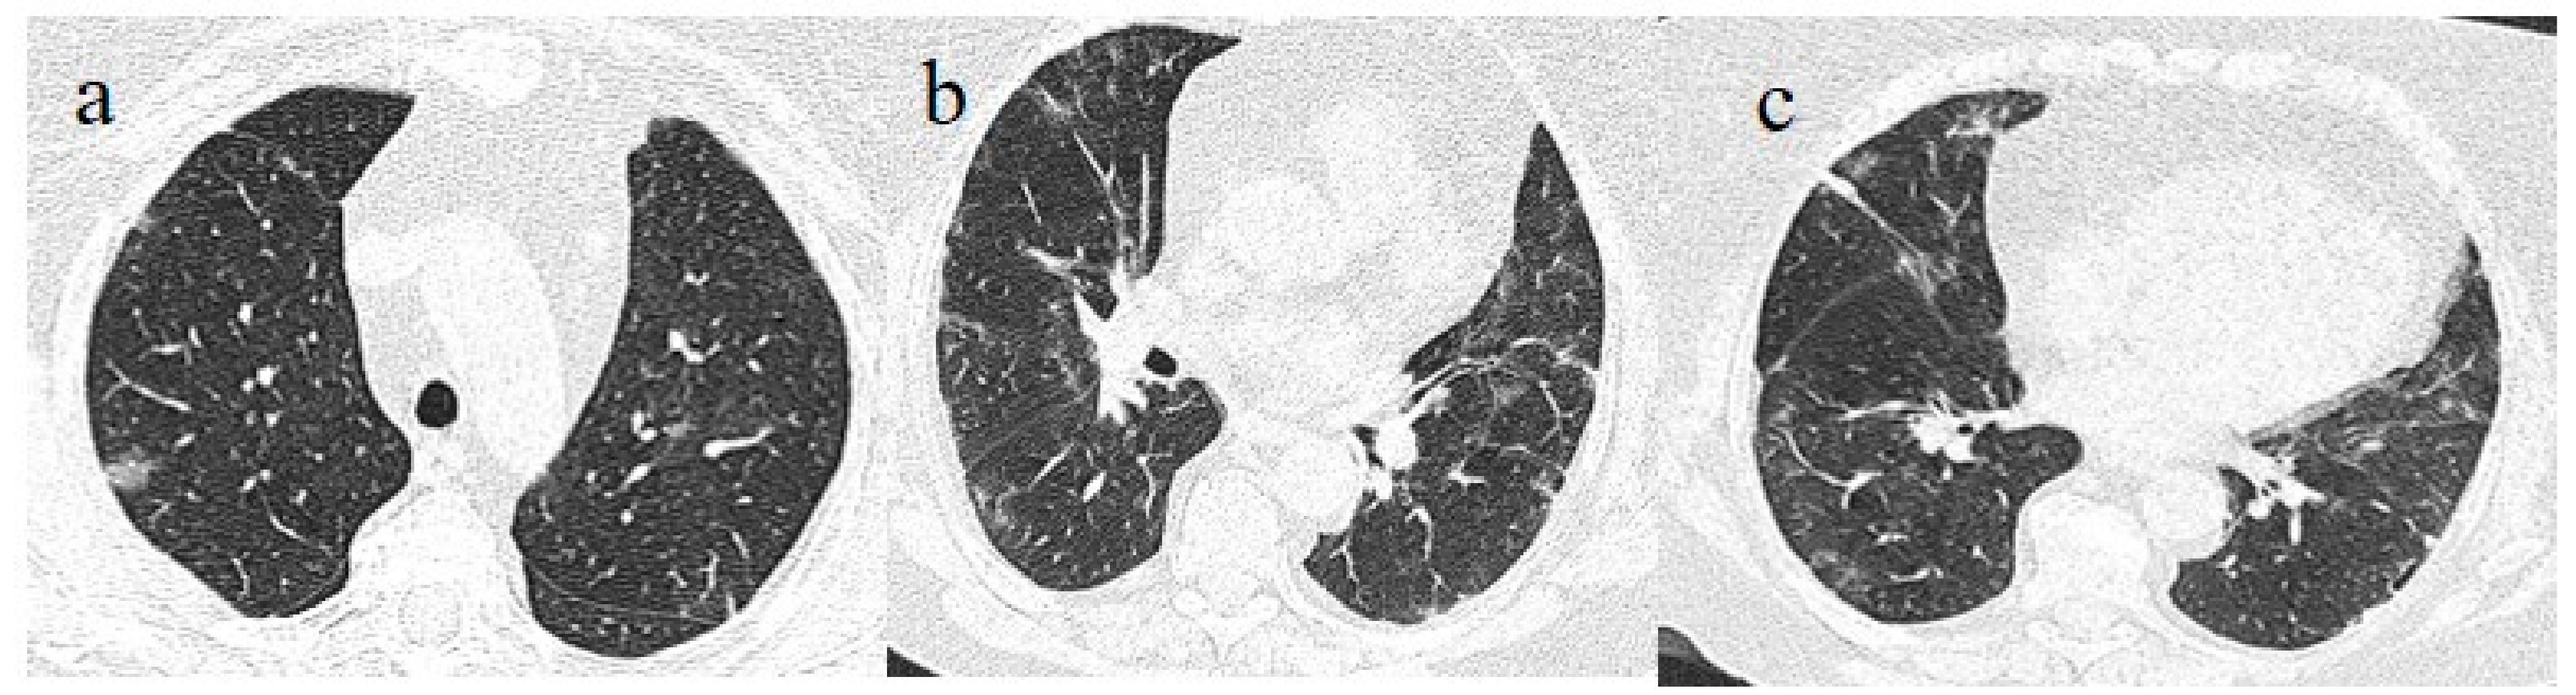

A chest Computed tomography (CT) performed in the emergency department showed a typical central and peripheral distribution of ground-glass opacity (GGO) COVID-19 pneumonia. The CT-SS score [21] showed a value of 13/20 (Figure 1).

The chest CT showed extended pneumonia, with an evolution in a crazy paving pattern and consolidation areas (CT-SS 16/20) (Figure 1). The patient died 5 days later.

Figure 1. (a,b) The basal CT with GGO in a typical peripheral and posterior distribution of COVID-19 pneumonia with a CT-SS of 13/20. (c,d) The chest CT performed 1 week later, showing more extensive pneumonia with a CT-SS of 16/20.